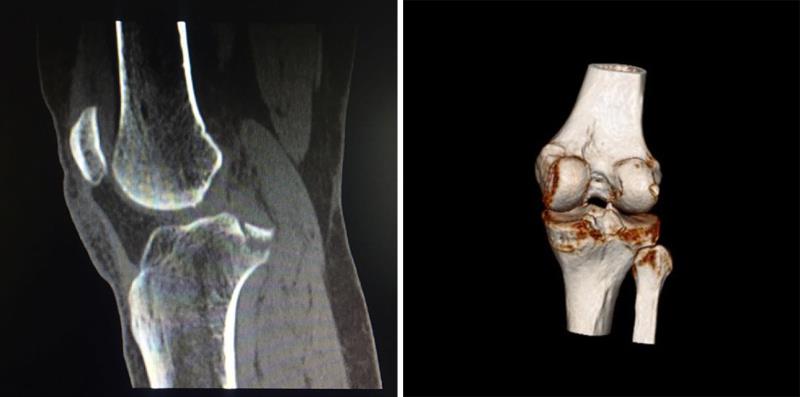

CT提示右膝后交叉韧带胫骨止点撕脱骨折